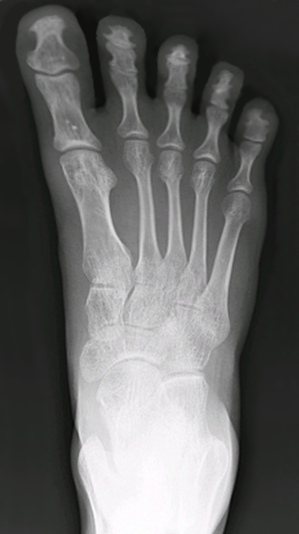

Notice how the toe box is tapered as if the shoe needs to be aerodynamic. This is purely aesthetic. Shoes should be shaped according to feet. In modern society, however, feet are shaped according to shoes:

On the left is the standard foot for a person who grew up wearing shoes. Notice how the bones are crooked instead of straight. On the right is a Photoshopped, hypothetical natural foot. The toes fan out.